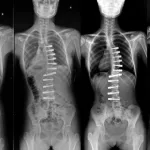

- Röntgen: Omurganın genel yapısını, kemiklerin hizalanmasını ve dar kanalın neden olabileceği yapısal bozuklukları görmek için kullanılabilir. Ayrıca, omurga hareketini değerlendirmek için özel fleksiyon ve ekstansiyon röntgenleri de çekilebilir.